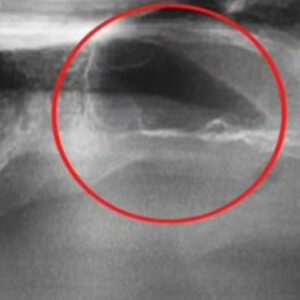

상악동 거상술 환자 실제 사례

부비동은 윗턱 위에 위치한 빈 공간으로, 일부 치아 뿌리가 여기까지 닿습니다. 치아를 발치한 후 남은 뼈가 얇아지면 임플란트를 안정적으로 심기 어려울 수 있습니다.

상악동 거상술로 인해 뼈를 식립하고 뼈의 두께가 (흰색 부분) 한층 두꺼워진 것을 확인할 수 있습니다. 이 후 충분한 검사 후 임플란트를 진행했습니다.